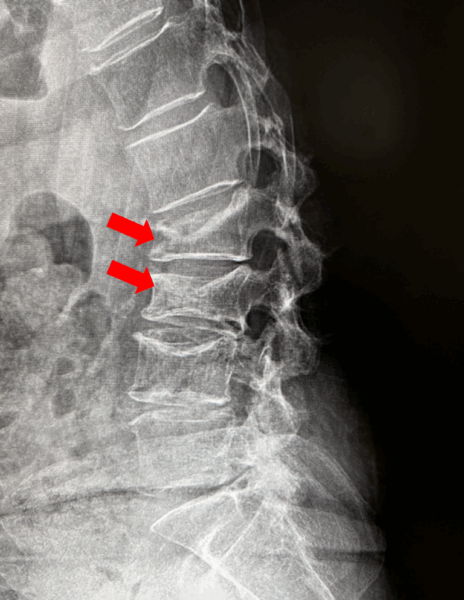

1.脊椎圧迫骨折とは

脊椎圧迫骨折は、転んだり尻もちをついたりした際、背骨に上下から強い力が加わることで起こる骨折(外傷性脊椎圧迫骨折)で、50歳以上の骨粗鬆症を持つ方に多くみられます。また、転んだりしていなくても、骨が脆くなっている場合は、いつの間にか骨折していることもあります(骨粗しょう症性脊椎圧迫骨折)。

背中が丸くなる(後弯姿勢)

椎体前方の圧潰により、後弯姿勢をとりやすくなります。